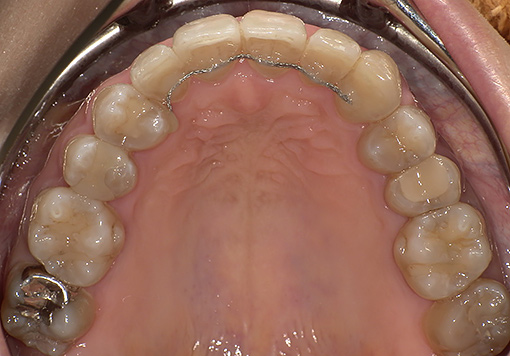

Case 03

before

after